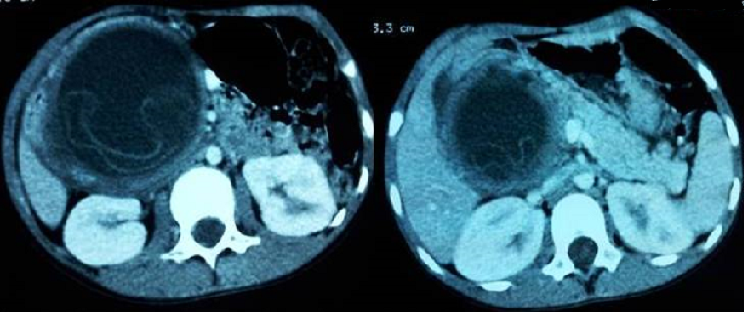

L'hydatidose est une maladie parasitaire très répandue dans le monde, notamment dans les pays d'élevage traditionnel. Sa localisation au niveau du pancréas est très rare, souvent révélée par un tableau de pancréatite aigue. Le diagnostic repose sur un faisceau d'arguments cliniques, biologiques et surtout radiologiques. Nous rapportons le cas d'une patiente âgée de 30 ans, sans antécédents pathologiques particuliers, admise aux urgences dans un tableau de douleurs épigastriques en barre avec vomissements, sans trouble de transit ni fièvre. Le bilan biologique a révélé une lipasémie à 10 fois la normale, et une hyperleucocytose à 13.500 éléments /mm3, permettant de poser le diagnostic d'une pancréatite aigue. Un scanner abdominal a été réalisé 48 heures après le début de la symptomatologie pour établir une stadification selon la classification de Balthazar, et a révélé une masse kystique de la tète du pancréas, bien limitée, arrondie, à paroi relativement fine et régulière, non rehaussée après injection du produit de contraste iodé. Cette masse renfermait des membranes flottantes faisant évoquer un kyste hydatique du pancréas. La sérologie hydatique réalisée était positive confirmant le diagnostic d'une pancréatite aigue compliquant un kyste hydatique du pancréas. La patiente fut adressée au service de chirurgie et a bénéficié d'une résection du dôme saillant associée à un drainage externe. Les suites post opératoires étaient simples.